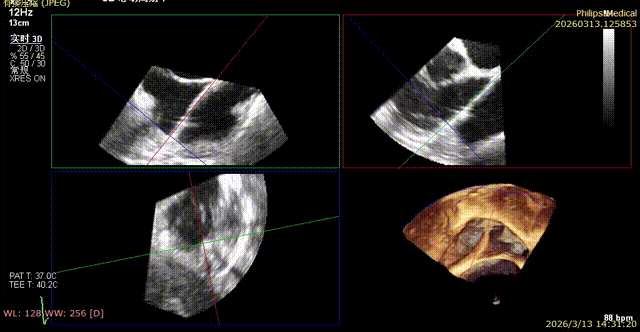

The first clip was initially implanted at the posterior‑septal commissure, which resulted in deformation of the coronary artery course. The first clip was released and repositioned toward the septal leaflet, with the clip arms opened to cross the posterior‑septal commissure before re‑implantation.

Initial DSA after clipping indicated compromised blood supply. The clip was therefore released, repositioned, and redeployed.

The second clip was deployed toward the septal leaflet, crossing the posterior‑septal commissure and positioned flush with the tricuspid annulus.

8. A second 14T device was selected and deployed following the same procedure.

During implantation of the second clip, anchoring was performed at the annulus near the leaflet base. Intraoperative DSA showed no impact on the coronary arteries, and good right coronary perfusion was confirmed after deployment.